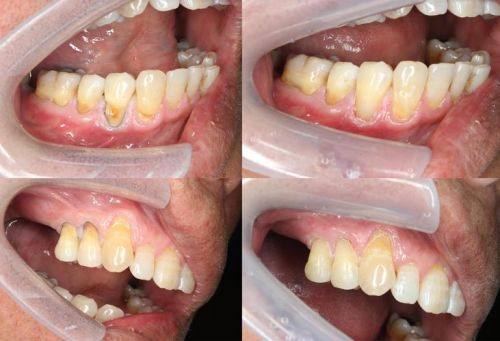

1. 种植牙:种植牙是西安弗莱堡口腔的特色与主打项目。医院设备齐全,拥有精良的数字化种植技术,能够借助完善的数字化设备精细测量患者口腔结构和骨骼情况,通过三维影像技术精细定位种植体位置,为种植方案设计提供详细的数据支持。同时,使用数字化导板确保种植体在手术中精细植入,减少手术时间,提高手术成功概率。此外,西安弗莱堡口腔还开展了all-on-4全口/半口即刻负重种植、穿颧穿翼疑难种植以及高龄种植技术等特色项目。其中,all-on-4全口/半口即刻负重种植可让患者在一次手术中完成多颗牙齿种植,大大节省治疗时间,还能提供更好的咀嚼功能和美观成效,提升患者生活质量。穿颧穿翼疑难种植则是针对牙槽骨萎缩、重度吸收等复杂疑难种植牙病例,西安弗莱堡口腔拥有经验多的医护团队和精良设备技术,能制定个性化治疗方案并取得良好成效。高龄种植技术方面,医院针对高龄患者有丰富的种植经验,医生团队会根据患者身体状况和口腔情况制定个性化治疗方案。

西安弗莱堡口腔的患者口碑良好,许多患者都对医院的服务和治疗成效给予了高度评价。有患者表示,在西安弗莱堡口腔完成牙齿矫正手术后,口腔状态得到了明显改善,牙齿变得整齐美观,笑容也更加自信了。还有患者在该医院完成了根管治疗,治疗过程中医生操作熟练、手法轻柔,让患者没有感到太多痛苦,而且治疗后口腔状态越来越好,未出现其他不适症状。此外,患者们还对医院的环境和服务态度赞不绝口,认为医院环境舒适整洁,医护人员热情周到,让患者在就医过程中感受到了家的温暖。